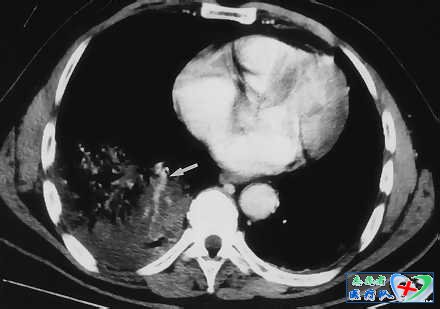

8、供血血管征:

供血血管征不同于血管造影中的肿瘤血管,该征象主要指的是在用CT扫描肺部时出现的肺部多个结节,并见血管结构穿行其间。该征象在肺部多排螺旋CT的高分辨率扫描时更为明显。但实际上动脉血管并没有真正穿行结节内,而是围绕结节走形。真正穿行其间的是肺静脉。该征的出现主要提示肺部的血源性感染,比如浓度栓子,也见于肺转移瘤。有学者研究发现,只有18%的结节有明确的肺动脉进入结节,58%的结节没有进入结节内,而是沿着其边缘走形,提示血管被结节所推移。对于少数穿行结节内部的动脉血管,有研究认为是动脉血管起初走形于两个小结节之间,随后由于这两个结节长大融合,使走形于其间的动脉血管由绕行成为“穿行”。